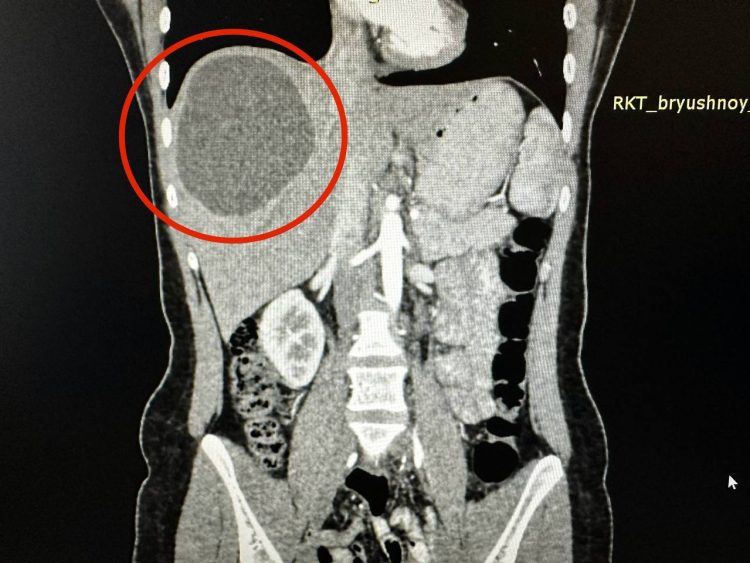

Как стало известно, девушку доставили в больницу с сильными болями в животе. Обследование показало, что у нее образовалась крупная киста размером 20 на 15 сантиметров, вызванная ленточными червями эхинококков.

Специалисты сначала решили применить химиотерапию для уничтожения паразитов. После чего ей провели хирургическое вмешательство. Однако, черви уже успели нанести ущерб печени, заставив врачей удалить почти треть органа.